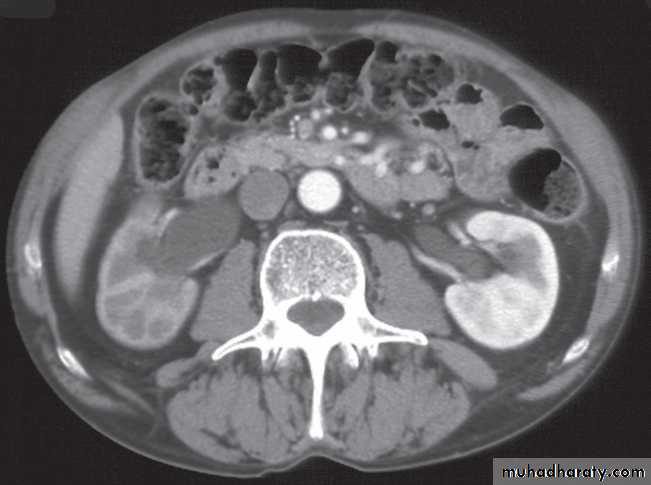

At CT:

-A typical simple renal cyst is a spherical mass with an imperceptible wall . The interior of the cyst is homogeneous with attenuation values similar to water.

At CT their fat content allows a confident diagnosis (Fig. 8.32b, c).

-Renal cell carcinomas are approximately spherical and often lobulated .With density similar to renal parenchyma or slightly less with often seen some areas of necrosis & calcification .